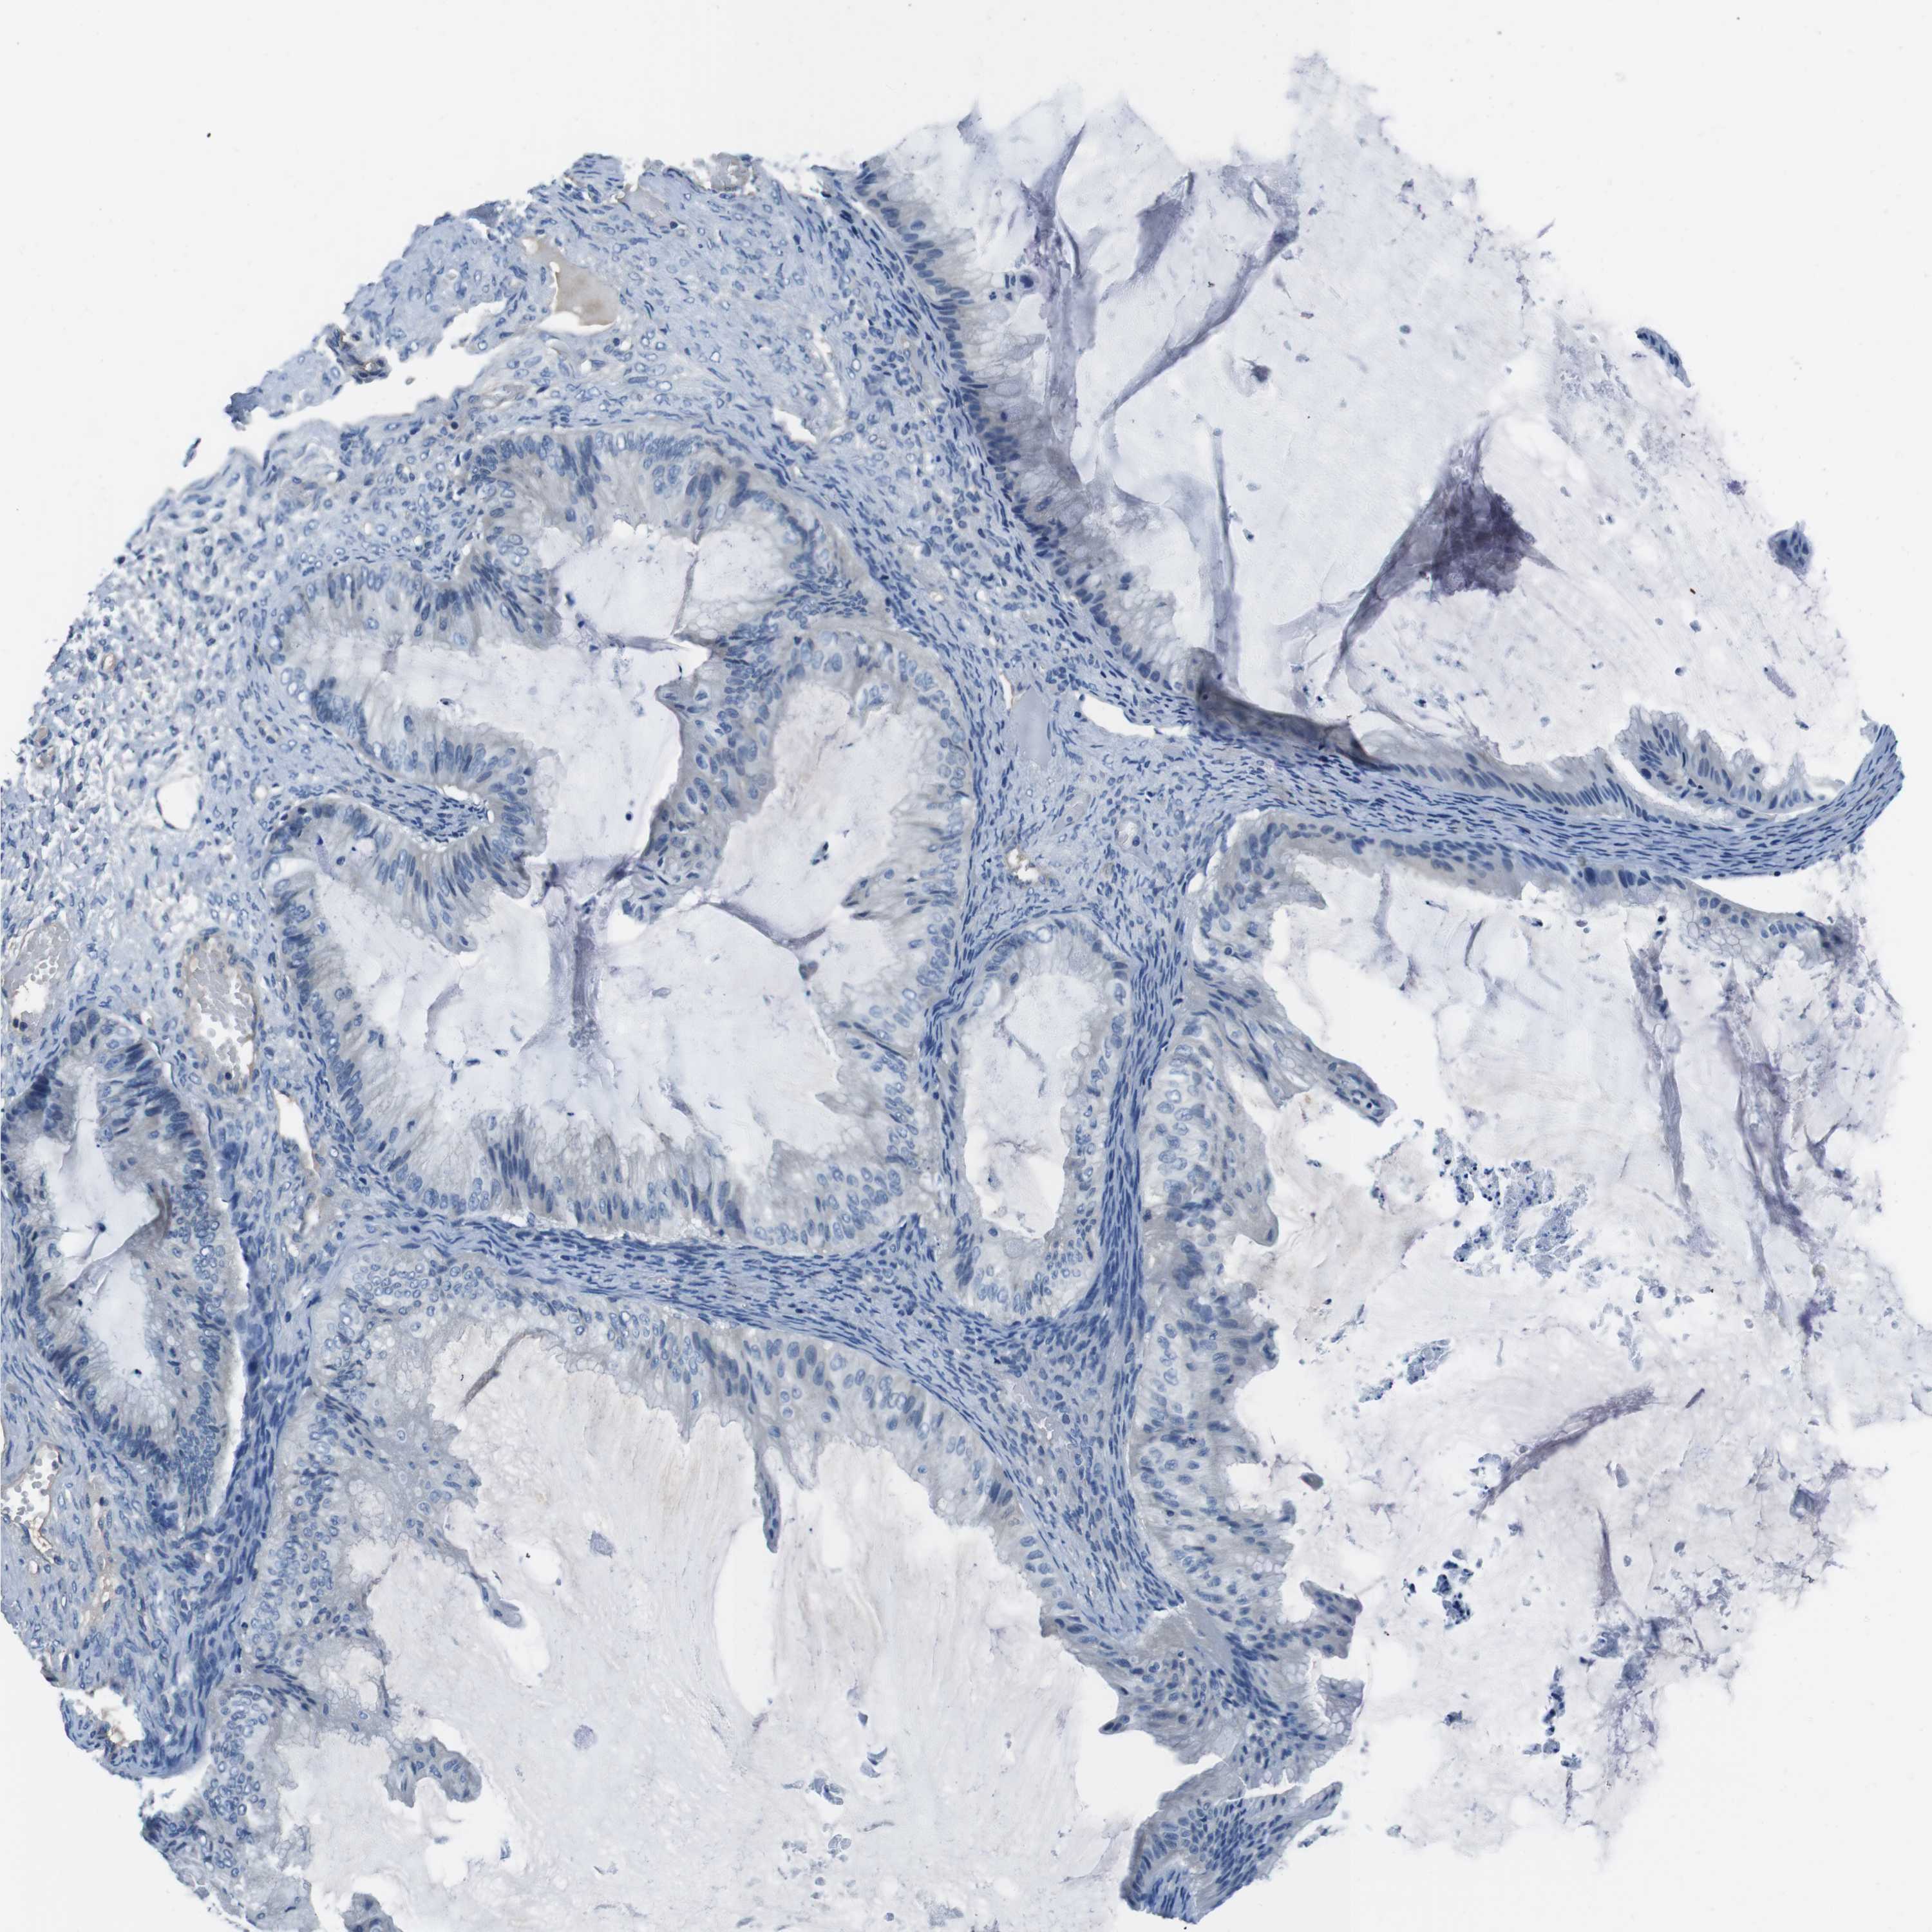

OVARIAN CANCER - Protein expressioni

A mouse-over function shows sample information and annotation data. Click on an image to view it in a full screen mode. Samples can be filtered based on level of antibody staining by selecting one or several of the following categories: high, medium, low and not detected. The assay and annotation is described here.

Note that samples used for immunohistochemistry by the Human Protein Atlas do not correspond to samples in the TCGA dataset.

Antibody stainingi

Antibody staining in the annotated cell types in the current human tissue is reported as not detected, low, medium, or high, based on conventional immunohistochemistry profiling in selected tissues. This score is based on the combination of the staining intensity and fraction of stained cells.

Each image is clickable and will lead to virtual microscopy that enables deeper exploration of all samples and also displays staining intensity scores, fraction scores and subcellular localization as well as patient and tissue information for each sample.

Antibody CAB015170